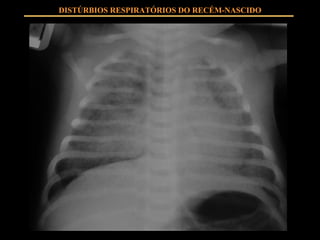

FISIOPATOLOGIA Insuficiente SURFACTANTE produzido por pneumócitos II Instabilidade alveolar com tendência ao colapso em expiração Extravasamento de líquido ao alvéolo Hipoventilação alveolar Shunts intrapulmonares Hipoxemia, hipercapnia DISTÚRBIOS RESPIRATÓRIOS DO RECÉM-NASCIDO

QUADRO CLÍNICO Estigmas de prematuridade Taquipnéia Esforço respiratório Cianose Hipoventilação DISTÚRBIOS RESPIRATÓRIOS DO RECÉM-NASCIDO